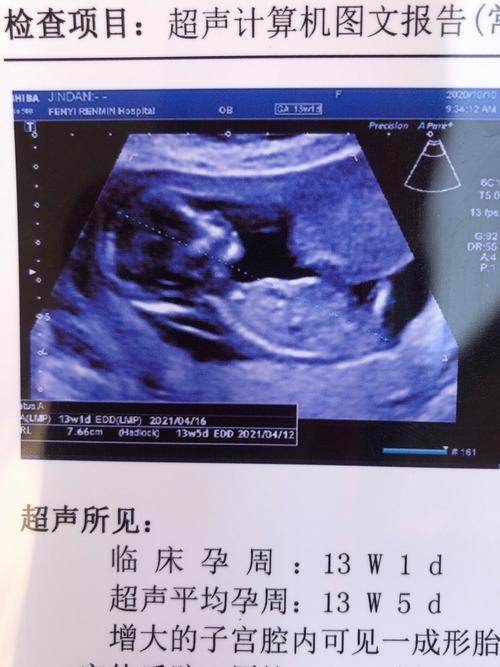

NT检查,全称是颈项透明层厚度检查,是孕早期(通常在11-13周+6天)进行的一项重要的早期唐氏筛查,它通过B超测量胎儿颈后皮肤层的液体厚度,来评估胎儿患有唐氏综合征(21-三体综合征)以及其他染色体异常的风险。

孕期13周NT检查是啥?-第1张图片-中州医学会

(图片来源网络,侵删)

2. 测量:医生会找到标准的胎儿正中矢状切面,清晰地显示胎儿的鼻骨、鼻尖、前额和颈项,B超机会自动或手动测量胎儿颈后皮下液体的厚度,这个厚度就是NT值。